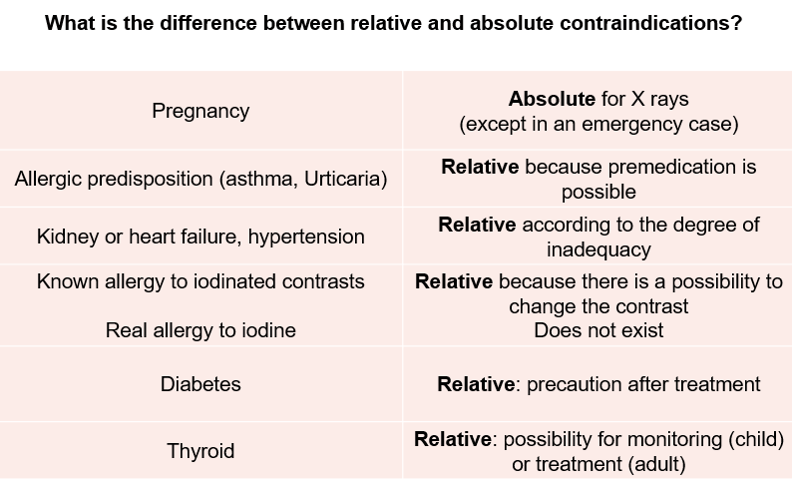

Contraindications

A contraindication is a condition or circumstance that would preclude the use of a CT scan with radiation OR the use of a contrast agent.

Relative or Absolute

An absolute contraindication is a situation that makes a particular treatment or procedure absolutely inadvisable. Relative contraindication means that caution should be used when two drugs or procedures are used together.

Great care must be used when injecting iodinated contrast to certain patients. Contrast-induced nephropathy otherwise known as deteriorated kidney function as a result of iodine-based contrast can have serious effects. Increased morbidity, as well as mortality rates, have been demonstrated in patients at risk. Those patients can include heart patients, diabetics, the elderly and those with known poor renal function and abnormal lab values. Certain precautions should be taken with gravid (pregnant) and lactating women.

Pregnant Women

CT examinations may be contraindicated in patients who are pregnant or suspected of being pregnant unless the procedure benefits out way the risks to the mother and the fetus. When possible an ultrasound should be used. If not possible, or in the case of trauma, a CT scan can be performed with the fewest slices and lowest doses possible to reduce the fetal dose. Always consult a radiologist prior to the examination. Gravid patients pose 2 main problems: